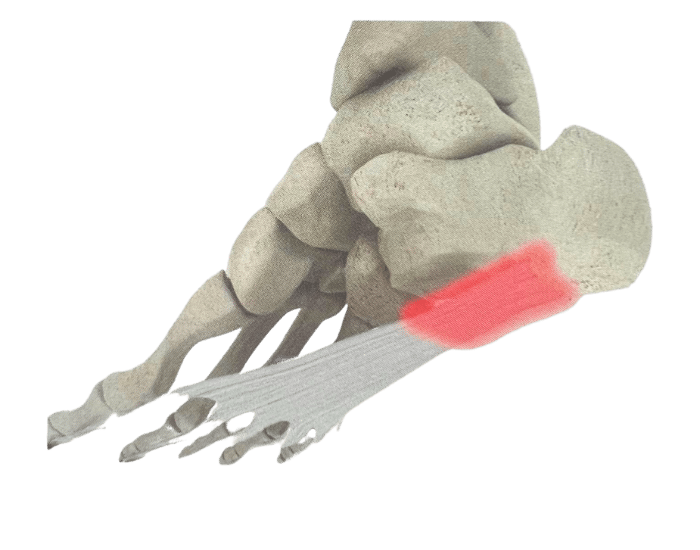

There are numerous reasons why you might need Custom Foot Orthotics. If you have pain in your foot, heel, knee or hip, have high arches or flat feet; or just being regularly on your feet and are getting any aches or pains in the feet or legs, or suffering from general foot pain while walking, running, playing sports or even at rest you qualify for Custom Foot Orthotics.